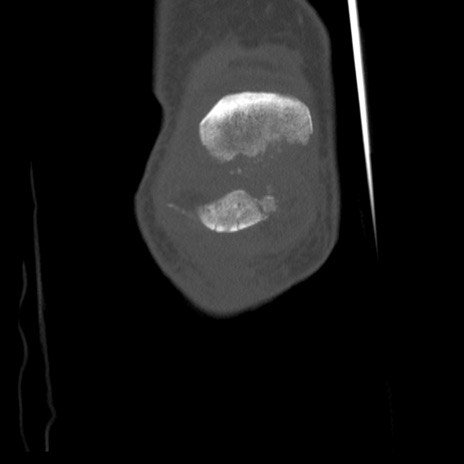

横断像